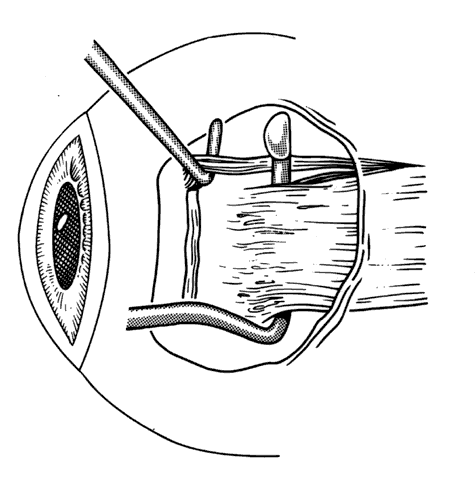

The incision should provide sufficient exposure and should be one the surgeon feels comfortable using. Our preference is to attempt to use a cul-de-sac incision whenever possible. This incision eliminates dissection through conjunctiva and anterior Tenon's capsule. When corrections require surgery on the superior rectus, conjunctiva is preserved for the remote possibility that a glaucoma filtering procedure may be required in the future (Figs. 13 and 14). The conjunctival incision can usually be made either through the old incision or just posterior to it.

Fig. 13. Incision is made through the conjunctiva. Conjunctiva is then dissected free from any adherent Tenon's capsule that overlies the site of the old muscle insertion. A blunt-tip Wescott scissors facilitates this dissection.

Fig. 14. This dissection is carried past the insertion until a hook is able to be passed under the muscle without restriction.